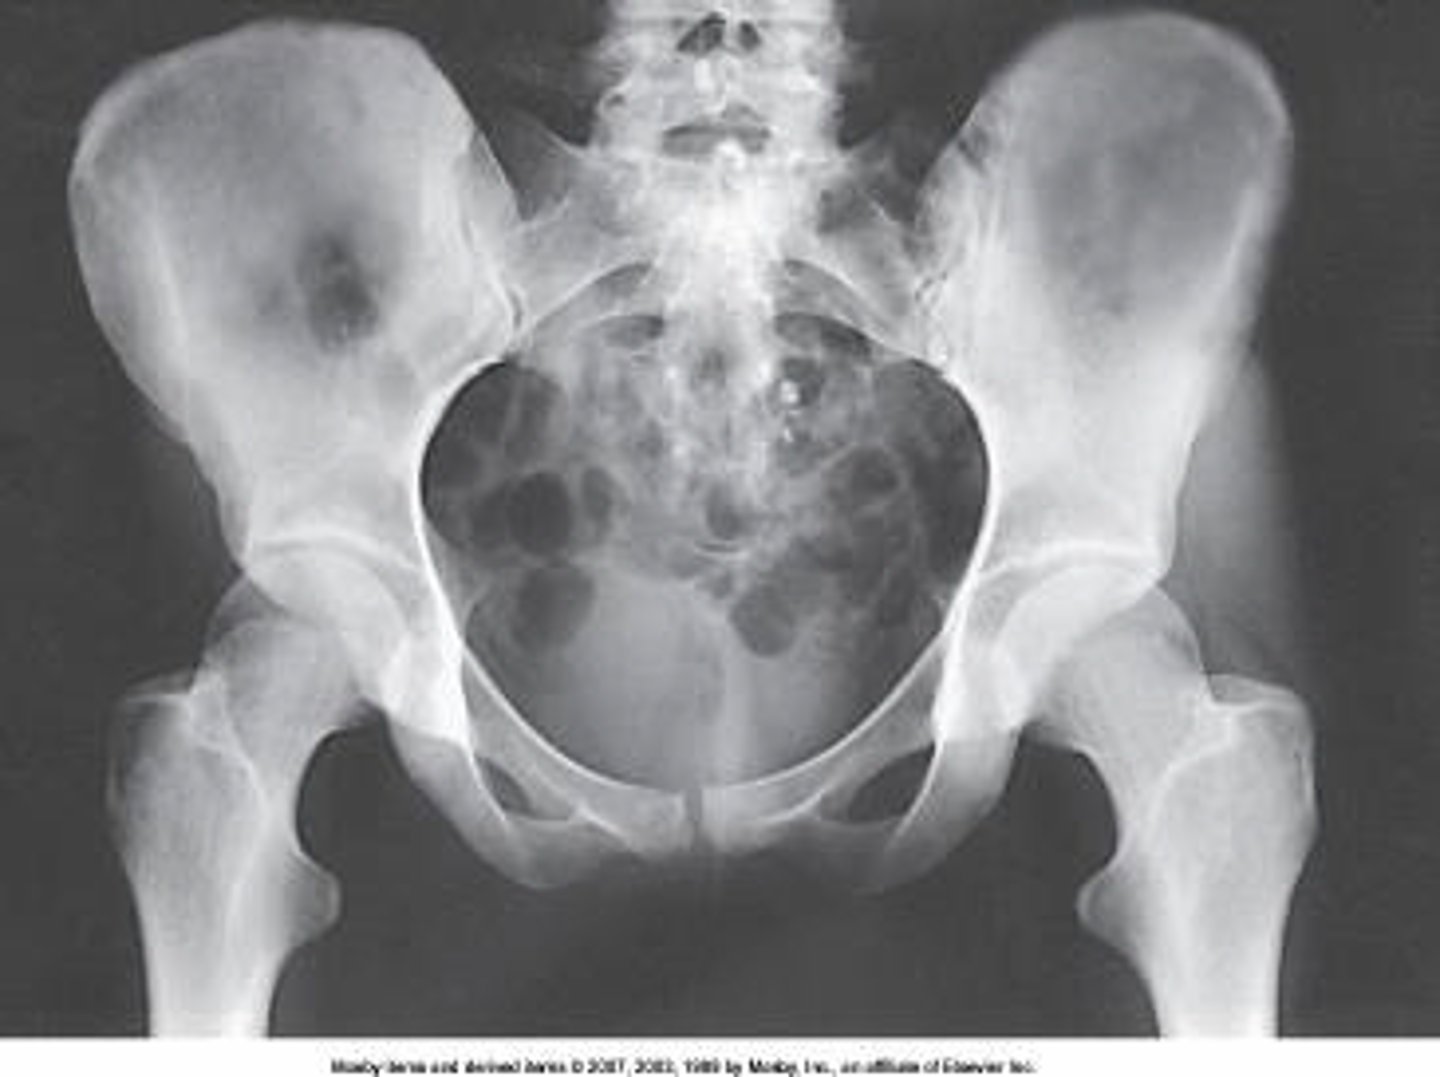

Identify the projection:

AP hip

AP oblique hip

AP pelvis

Lateral hip

Identify the anatomy marked A:

Pubis bone

Head of the femur

Femoral neck

Ischial tuberosity

Coccyx

The anatomy marked with #6 is the:

Acetabulum

Lesser trochanter

Obturator foramen

Greater trochanter

Ischial spine

Identify the anatomy marked with #7:

Pubic symphysis

Pubic bone

ilium

Is this pelvis rotated?

Yes

No

I'm not sure

The anatomy marked with #3 is the: